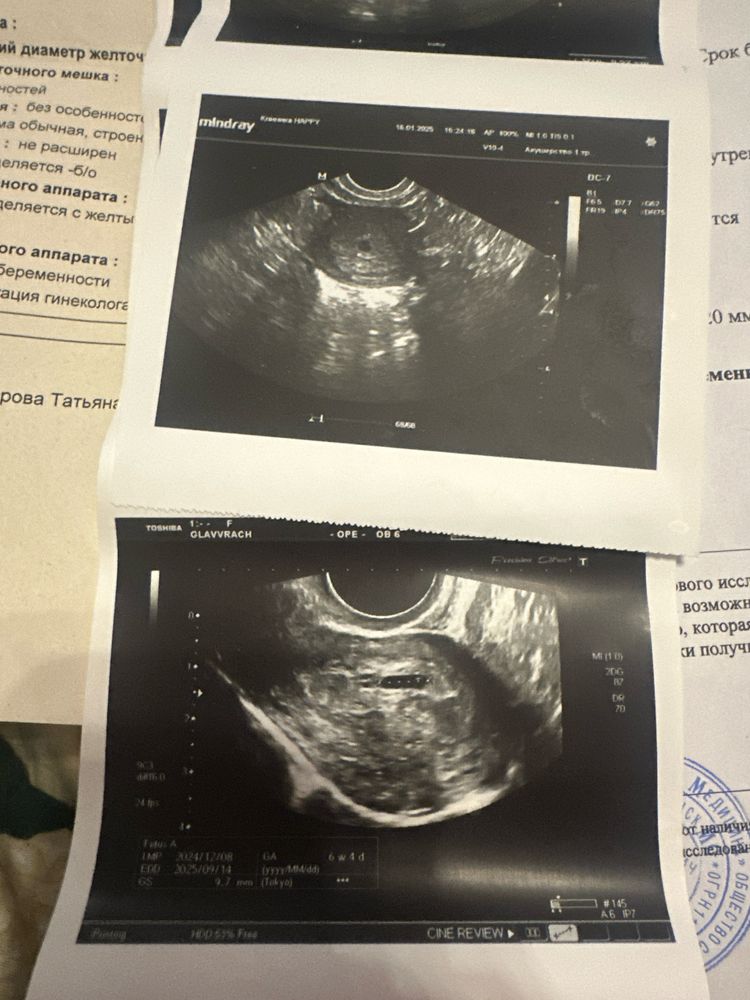

Сравнение УЗИ через неделю

Ктг Результаты УЗИ.